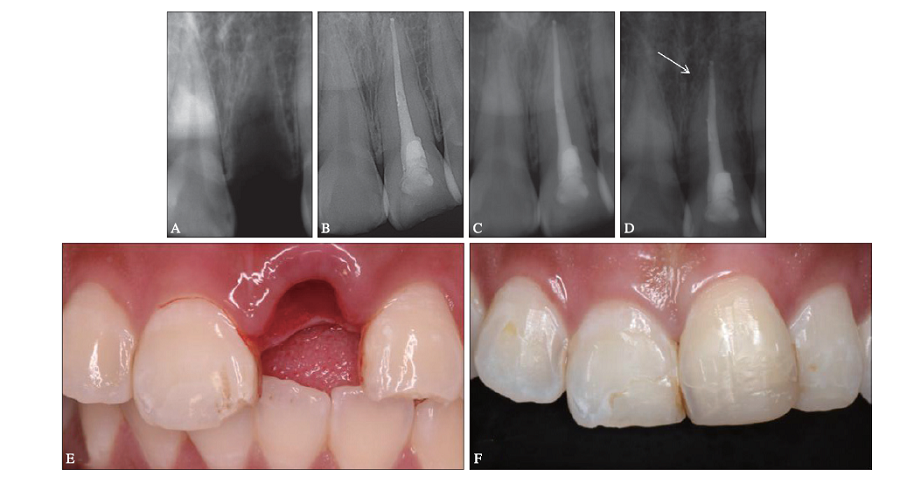

图 2

根管内部分闭锁 A:完全脱位后全景片截图,示11牙缺失,未见明显牙槽突骨折;B:再植1个月后X线片,示11牙牙周膜宽度正常,根尖孔开放(箭头),髓腔宽大,根尖未见明显异常;C:再植9个月后X线片,示根管壁较图B增宽,髓腔变窄,根尖孔继续发育(箭头),根尖区未见明显异常,临床牙髓电活力测试同对照牙;D:再植3年后X线片,示11牙根尖孔未闭合,根管壁增厚,髓腔较正常牙缩窄,根尖形态不规则(箭头),临床牙髓电活力测试数值为38,较对照牙略迟钝;E:再植1个月后口内照;F:再植3年后口内照。"